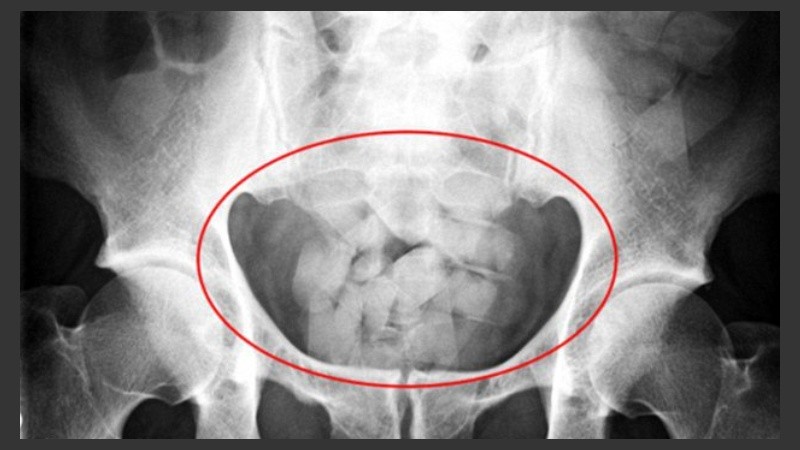

"Tuvimos el caso de una mujer. Tenía 81 cápsulas de cocaína en su cuerpo. Para tomar dimensión, cada una tiene cuatro centímetros de largo y uno de diámetro. Llevaba poco menos de un kilo", añadió.